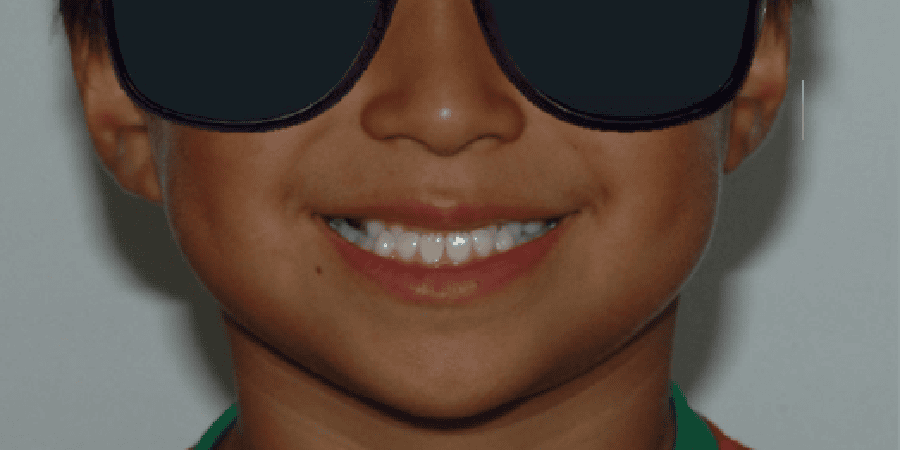

Before